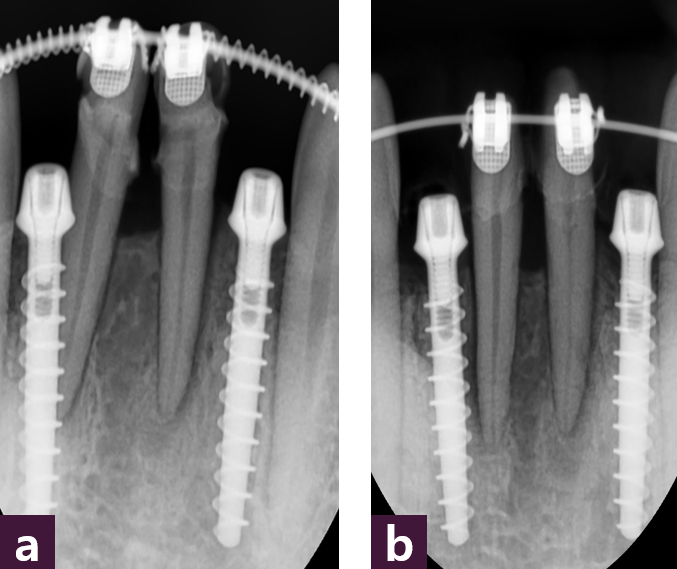

36세 여성 환자로 재보철을 하기 위하여 내원하였으나 공간이 충분치 않아 부분교정 후 임플란트 식립 계획을 세웠다 [그림 7].

임플란트 수술 시에는 Magic GPS를 이용하여 뼈 중앙에 MagiCore를 최소 침습적으로 식립하였다 [그림8].

최소침습적 방법으로 Magi Core를 식립한 후 치근 방향을 교정하였다 [그림 9].